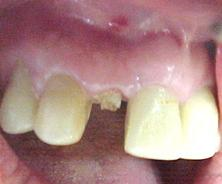

Figura n°3. Esta é a fotografia antes da cirurgia para implante. A imagem não ficou boa, mas pode-se notar com atenção uma linha de fratura iniciando na região vestibular com direção à distal.

Antes de ser realizada a cirurgia, a paciente foi moldada, feito modelo de estudo para confecção de uma coroa provisória e do guia cirúrgico. Os detalhes protéticos serão discutidos no final da parte cirúrgica.

Antes da cirurgia a paciente foi submetida uma anti-sepsia bucal com bochechos de Periogard seguido de uma ampla profilaxia com o jato de bicarbonato de sódio.

Figura n°4. Esta fotografia mostra a incisão inicial, intra-sulcular, com lâmina N15, para melhor aproveitamento do tecido mole na reconstrução da gengiva marginal do implante. O retalho deve sempre ser total, ou seja, muco-perióstico.